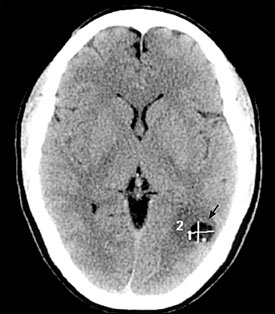

Sau khi thăm khám và điều tra bệnh sử, chụp cắt lớp vi tính có hoặc không có bơm thuốc cản quang đường tĩnh mạch là bước đầu tiên trong chẩn đoán các ca bệnh nghi ngờ ATSL thần kinh. CT não có hoặc không có thuốc cản quan sẽ cho thấy hình ảnh các tổn thương điển hình của ATSL đường kính nhỏ hơn 20mm và không có hình ảnh phản đứng giữa (no midline shift) là hình ảnh gợi ý cao cho thể ATTSL thần kinh (neurocysticercosis). Phần scolex, hoặc phần giác hút của ấu trùng cũng có thể nhìn thấy; đây là đặc trưng bệnh của ATSL thể thần kinh.

Hình 2. trên hình ảnh CT có nang của ATTSL thể thần kinh trong nhu mo não đặc | Hình 3. hình ảnh cộng hưởng từ cho thấy các nang của ATSL thể thần kinh trong nhu mô |

Số lượng, kích thước và vị trí có nang xuất hiện cũng như giai đoạn chu kỳ của nang sán, có thể xác định và có thể tác động đến việc quyết định điều trị. Các nang là các hình ảnh tổng thương dạng điểm có thể phát triển và tồn tại được, nang không bị thoái hóa. Các tổn thương dạng nang chỉ ra biến tính hoặc thoái hóa có một vài phản ứng viêm bao quanh. Cuối cùng, các nang hình thành calci hóa là một bằng chứng các nang đã tồn tại lâu có thể đã chết. Chăm sóc phải được tiến hành khi có thể còn nghĩ đến nhiều nguyên nhân khác (lao, bệnh ký sinh trùng khác, di căn từ nơi khác đến, hoặc ung thư nguyên phát của não hoặc hình ảnh abces não) khi một tổn thương tìm thấy trên phim chụp cắt lớp.